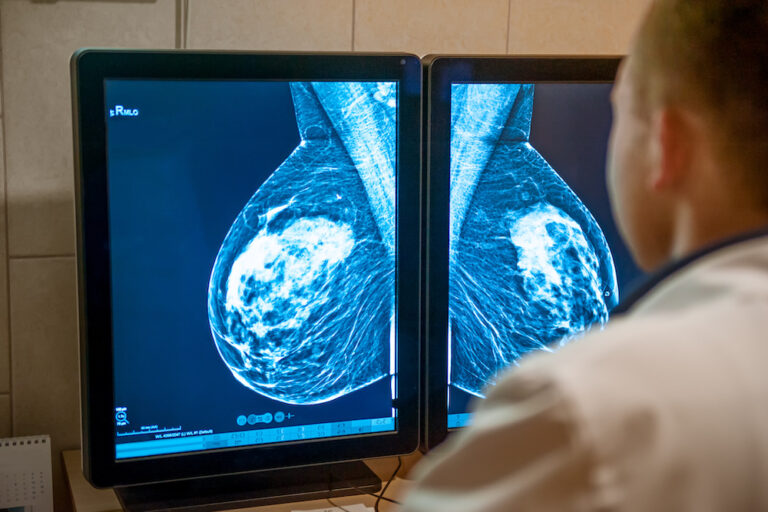

El principal partido de la oposición en el Consell de Formentera, Gent per Formentera (GxF), defenderá este jueves en el pleno una proposición para reclamar más transparencia y control en los programas de cribado de cáncer, especialmente en el de cáncer de mama, tras las incidencias detectadas recientemente en varios puntos del Estado.

La formación insta al Govern balear y al IB-Salut a que hagan pública y accesible toda la información relativa a estos programas, desde el número de pruebas realizadas hasta los tiempos de espera y las medidas adoptadas para mejorar la atención a los pacientes.

El grupo recuerda que la falta de transparencia “pone en cuestión la calidad y la seguridad de los programas de detección precoz” y reclama una revisión urgente de los protocolos.